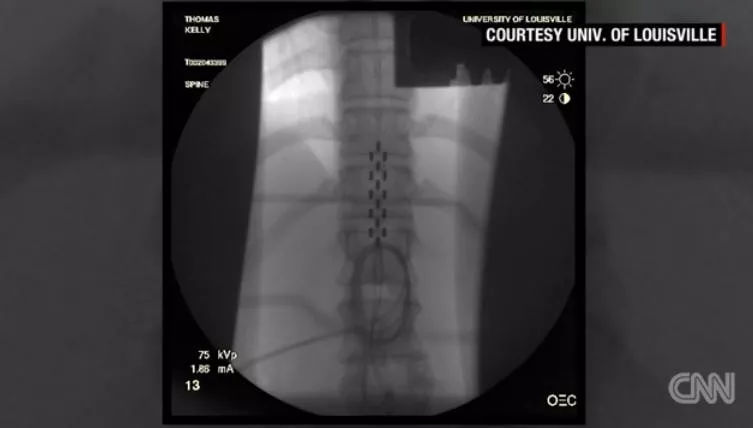

Thomas通过手术植入脊髓刺激装置,之后,接受了为期10月的每周五天每天两次的高强度物理治疗,上午为走路,下午为站立。

在Thomas脊髓下部的硬膜外植入刺激装置,这种刺激装置能够使受伤部位下面的神经元接收到大脑发出的信号

刺激装置通过一遥控器来进行控制,Thomas将遥控器固定在腹部。当处于开启的状态时,Thomas才能够移动其下半身,或是走路